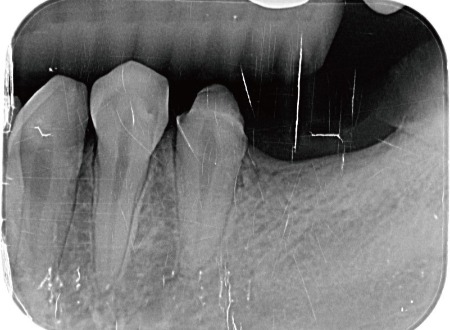

圖示:左下後牙區X光片,箭頭處為假牙與臼齒殘根

這可能是因爲是她早期左下的臼齒缺牙,當時在其他診所是用傳統牙橋修復。

傳統牙橋的缺點除了是前後牙齒需要犧牲齒質磨小才能印模製作以外,牙橋底下也會產生清潔死角,導致難做到良好的清潔,很容易發生再蛀牙或是牙周疾病等後遺症,久而久之後面的牙齒蛀斷了成為殘根。